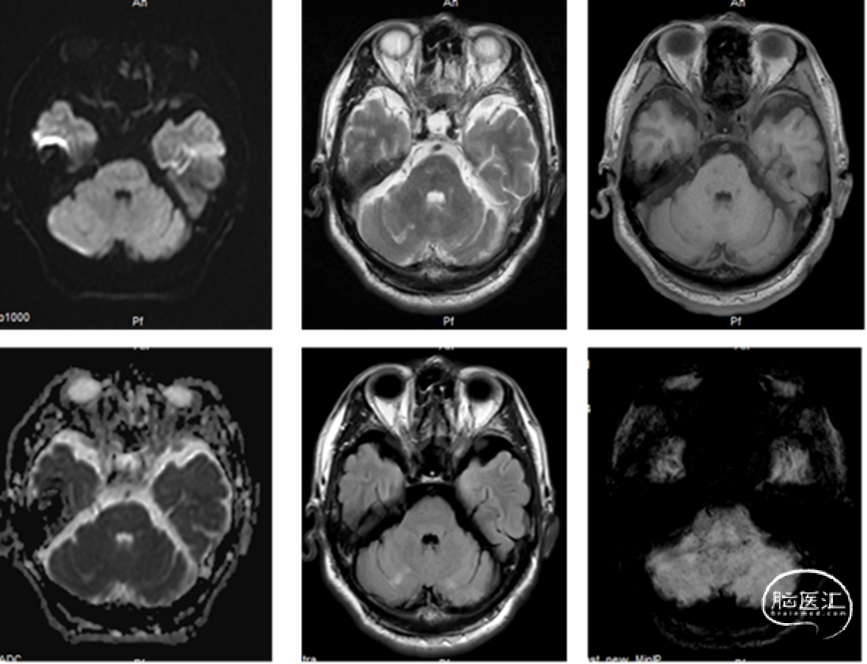

300cm微导丝携Gateway球囊到位,行球囊扩张及预扩张后造影。

小结和体会

1、本例患者反复出现神经功能障碍,血管评估提示双侧椎动脉V4段均为重度狭窄,左侧狭窄位置位于发出小脑后下动脉下方,紧邻小脑后下动脉,同时左侧小脑后下动脉起始段存在有重度狭窄,相对粗大。

2、右侧椎动脉V4段血管狭窄附近未见有明确血管分支,因此手术选择了行右侧椎动脉V4段球囊扩张及支架置入术,因双侧椎动脉V4段狭窄以远椎动脉及基底动脉汇合处血管良好,因此右侧椎动脉V4段狭窄处支架置入术后病人右侧椎动脉及远端基底动脉血流明显改善外,同时也可见到左侧椎动脉V4段逆向显影至左侧小脑后下动脉。同时避免了左侧椎动脉支架置入术中对左侧小脑后下动脉的影响导致小脑后下动脉缺血事件发生的可能。

3、Gateway球囊为半顺应性球囊,推送性能良好,术中缓慢扩张,可减少球囊移位、血管变形及夹层等,为后续支架置入提供了良好的条件。

4、EZ支架通过性好,释放顺畅,径向支撑力强,支架贴壁良好。

1. 本例患者为症状性双侧椎动脉V4段重度狭窄,即症状性颅内动脉粥样硬化性狭窄(sICAS),双侧后交通动脉缺如,缺少代偿机制。经强化内科药物治疗仍有缺血事件发作,根据目前诊疗指南及专家共识,具有介入治疗的手术适应症,并经术前各项检查未发现手术禁忌症。

2. 患者为双侧椎动脉病变,且双椎直径差别不大,无显著的优劣之分,因此在手术策略上就有三种选择:单做右侧椎动脉、单做左侧椎动脉及同时做双侧椎动脉。术者详细分析了双侧椎动脉的情况(PICA分支情况、双椎融合处形态、基底动脉近端形态),优先选择了能够有效改善供血且安全性最高的右椎方案。

3. 手术器材选择恰当,充分发挥了同轴球囊导管和自膨式开环支架的优点,操作过程简洁、准确,手术效果满意。